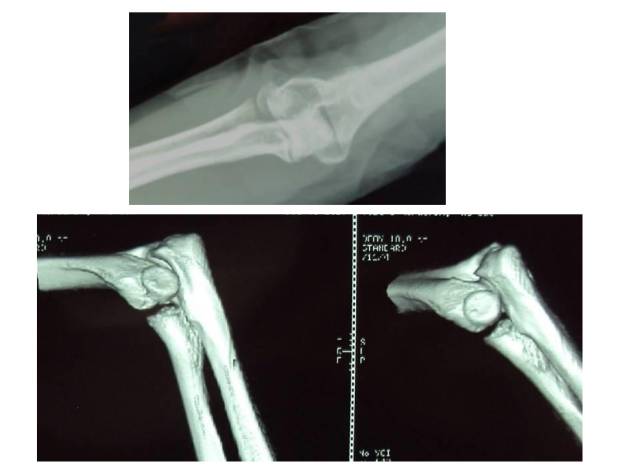

冠突是一个非常重要的稳定结构

• Ⅰ型和Ⅱ型单纯冠状突骨折,发生后方半脱位的风险很小,允许早期活动

• 即使单纯Ⅲ型骨折,在很小的生理应力下也有可能发生后方半脱位,特别是在屈肘60°~105°,支持对Ⅲ型损伤ORIF